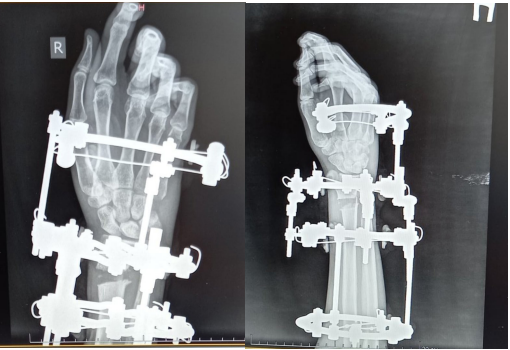

The existing progress in medical science allows us to revise the established views on the issue of DMLK treatment, suggesting the use of technically improved equipment, other methodological aspects at the preoperative stage of working with a patient, and much more. However, it should be noted that, despite all of the above, the use of external osteosynthesis, despite its popularity, does not solve the issues of minor post-traumatic deformity (1-2 mm), which causes osteoarthritis and arthritis of the affected segment, and also complicates the X-ray observation of DMLK and postpones the start of rehabilitation measures. Thus, the use of transosseous osteosynthesis according to Ilizarov has a number of immediate advantages (Figure 2 & 3).

Figure 3 Radiographs of the wrist joints of the patient D. 19 years old at the stage of treatment with the device G.А. Ilizarov.